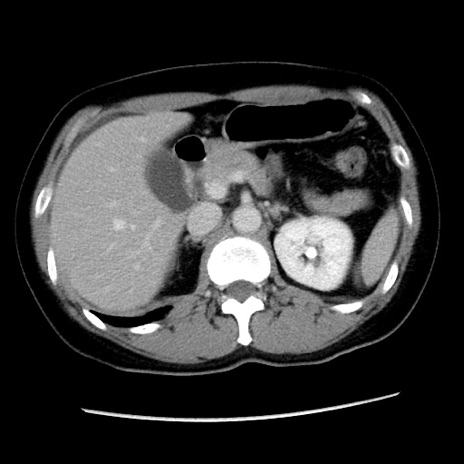

症例10(横断像)

【症例】 50歳代女性

【主訴】 腹痛

【現病歴】前日生レバーを食べた。今朝に排便あり。 昼前に突然発症の腹痛を生じ、当院救急外来を受診した。

【既往歴】 子宮筋腫にてで子宮全摘後

【身体所見】 意識清明、腹部:平坦、軟、下腹部やや左を中心に圧痛・反跳痛あり、筋性防御あり

【データ】WBC 7800、CRP 0.07